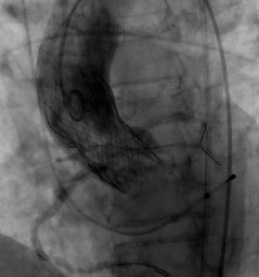

Figure 2. After deployment of the CoreValve Evolut R device, the coronary guide catheters were withdrawn while maintaining wire access to the coronary arteries. Aortography was performed, demonstrating patency of the coronary ostia.

In the case of a patient with low takeoffs of the coronary ostia and narrow sinuses of Valsalva (Figure 1), the preference at our institution is to protect the potentially affected coronary arteries with coronary guidewires prior to placement of the valve. We withdraw the guide catheters above the level of the leaflet insertion of the prosthetic valve, leaving the guidewire in place, so that patency of the coronary ostia can be clearly visualized. After deployment of the transcatheter valve, aortography is performed to demonstrate patency of the coronary arteries (Figure 2).